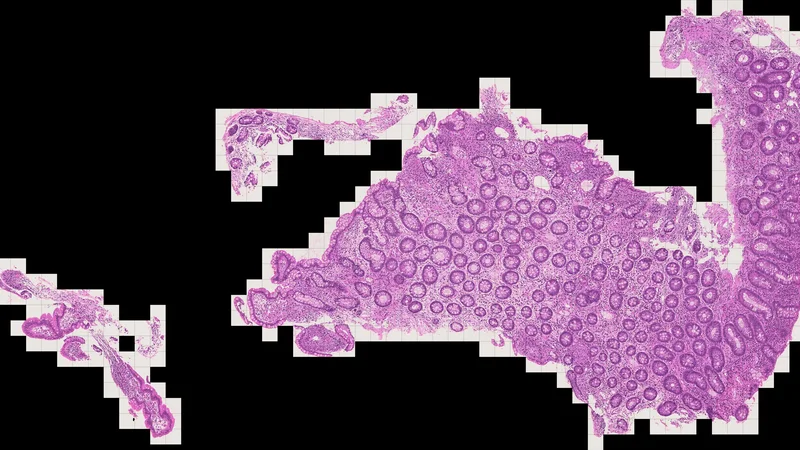

The effective application of foundation models to translational research in immune-mediated diseases requires multimodal patient-level representations that can capture complex phenotypes emerging from multicellular interactions. Yet most current biological foundation models focus only on single-cell resolution and are evaluated on technical metrics often disconnected from actual drug development tasks and challenges. Here, we introduce EVA, the first cross-species, multimodal foundation model of immunology and inflammation, a therapeutic area where shared pathogenic mechanisms create unique opportunities for transfer learning. EVA harmonizes transcriptomics data across species, platforms, and resolutions, and integrates histology data to produce rich, unified patient representations. We establish clear scaling laws, demonstrating that increasing model size and compute translates to improvements in both pretraining and downstream tasks performance. We introduce a comprehensive evaluation suite of 39 tasks spanning the drug development pipeline: zero-shot target efficacy and gene function prediction for discovery, cross-species or cross-diseases molecular perturbations for preclinical development, and patient stratification with treatment response prediction or disease activity prediction for clinical trials applications. We benchmark EVA against several state-of-the-art biological foundation models and baselines on these tasks, and demonstrate state-of-the-art results on each task category. Using mechanistic interpretability, we further identify biological meaningful features, revealing intertwined representations across species and technologies. We release an open version of EVA for transcriptomics to accelerate research on immune-mediated diseases.